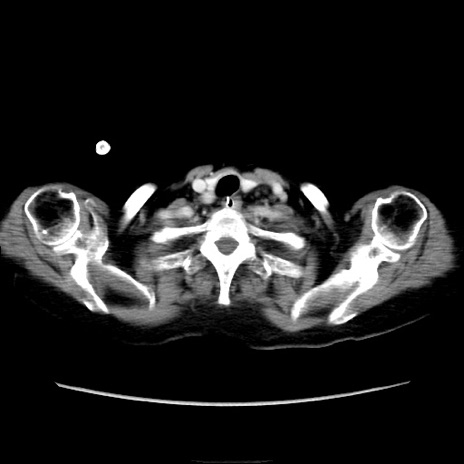

他院CT

横断像

冠状断像